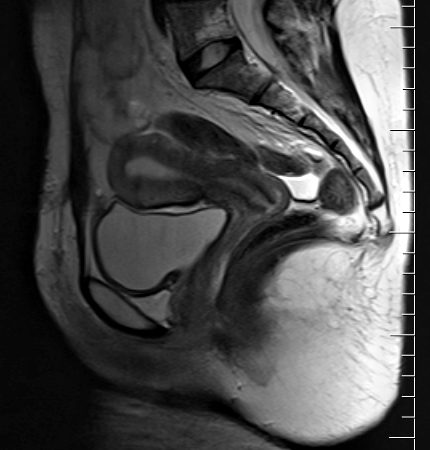

МРТ органов таза девушки в сагиттальном срезе

Девушка в сагиттальном разрезе

Особенность анатомии девушек подразумевает постоянное сообщение полости влагалища с внешним миром, что в свою очередь сделало их зависимыми от состояния микрофлоры. У мужчин не так.

В отличие от мужчин с достаточно длинной уретрой уретра женщин более короткая и широкая. Выход расположен в непосредственной близости от влагалища с его обильной микрофлорой. Плюс тут же в непосредственной близости расположено анальное отверстие с соответствующей микробиотой толстого кишечника, которая ведёт себя как патогенная, если закрепляется где-то ещё. Всё это приводит к тому, что любой перекос микробиома или проблемы с гигиеной немедленно приводят к воспалительным процессам со стороны мочевого пузыря и влагалища.